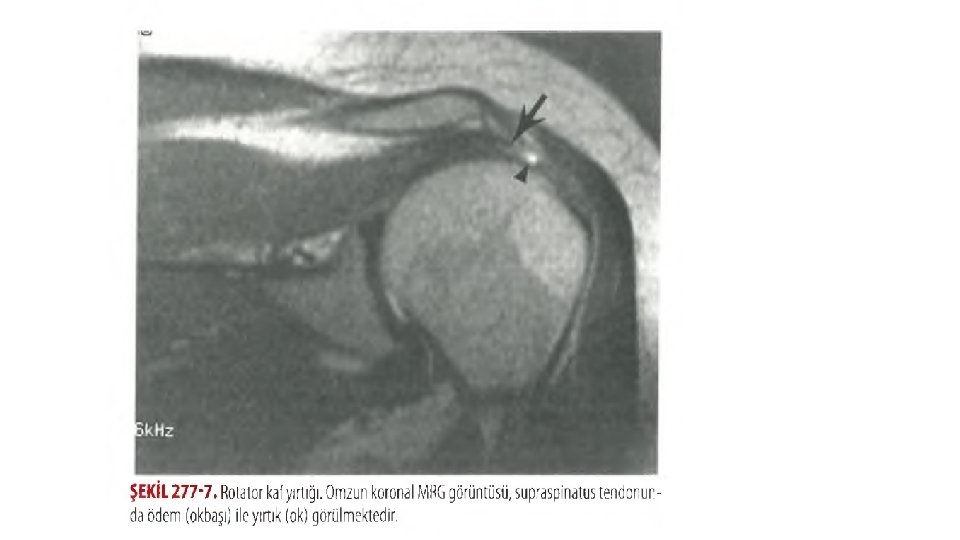

TANI • TAM YIRTIK ? • KISMİ YIRTIK ? • İNFLAMATUAR ROTATOR ? AYRIM ZOR v. Hiçbir radyografik bulgu bir akut rotator kaf yırtığı için tanısal değildir ve tanı klinik bulgulara bağlı olmalıdır. MRG, USG ve artrografı en hassas yöntemler.

ROTATOR KAF YIRTILMALARI 1. Akut tramvatik yaralanma%10(cisim yakalama, hiper ektansiyon abduksiyon) 2. Kronik yaralanma 3. Rotator kafin kronik sıkışmasının (evre 3) akut ekstansiyonu v 40 yaş üzerindeki hastaların ilk çıkıklarda, bunun %57’si akut rotator kaf yırtılması görülür.